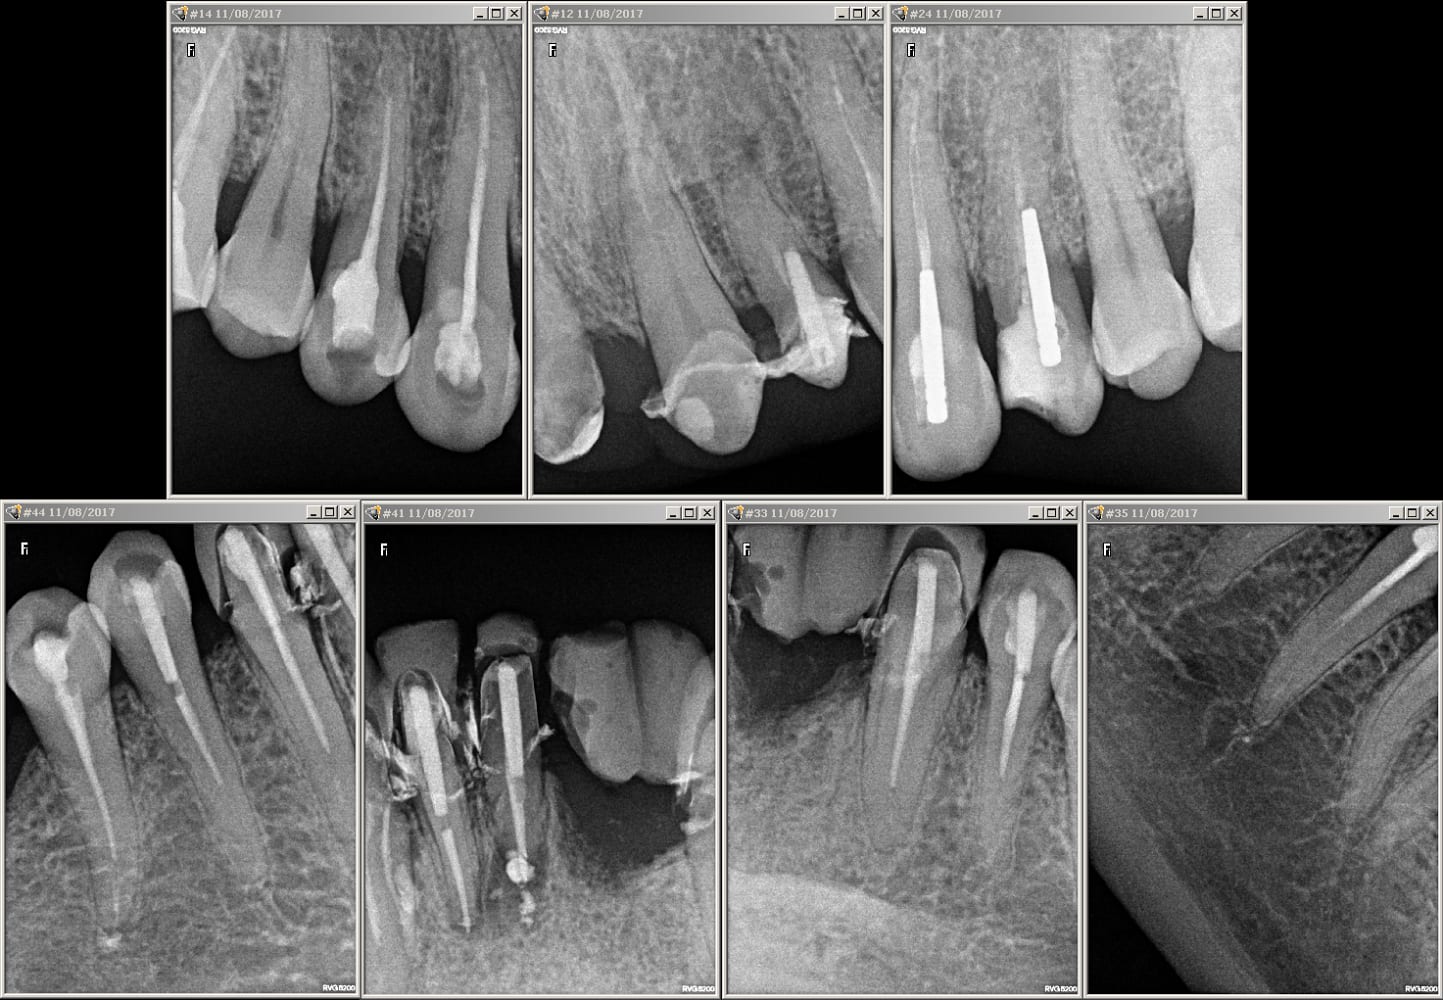

Bon et bien le haut maintenant...

Img 1606 y7zgvi - Eugenol

Img 1610 lptn89 - Eugenol

Img 1615 rpdoqy - Eugenol

Img 1653 obrh1p - Eugenol

Img 1613 ytxave - Eugenol

iyaudat

14/08/2017 à 17h18

Treponem écrivait:

------------------

> bof, ça se trouve, il n'a même pas vu que c'était une couronne :)

Tout a fait treponem, en fait il y avait un début de cavité sur cette dent puis finalement abandonné lorsqu'il a vu la céramique j'imagine, car la cavité ne fait meme pas un mm de profond, l'armature n'est pas percée et donc aucun rte n'a été fait et nous voyons sur la radio l'endo initiale qui elle est bien plus ancienne, puis il a rebouché avec un cavit d'ou l'impression d'un rte sur les premières photos